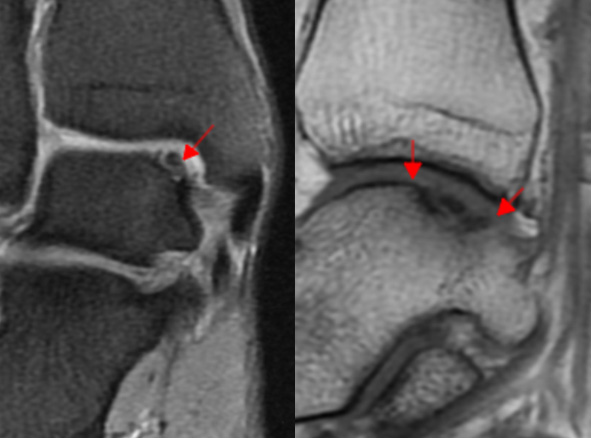

거골의 내측부 연골 병변에 대해서 관절경을 통해 미세천공술과 콜라겐 주입술을 시행하였으며,

수술 5개월째 결손 부위에 연골이 잘 생성되어 있는 소견이 관찰되었습니다.